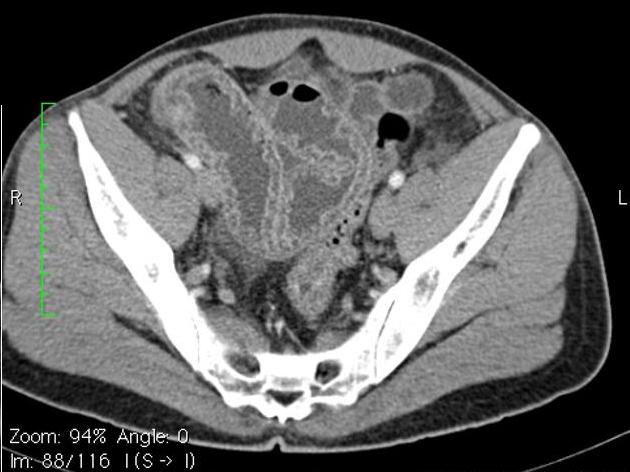

Epaissisement hyper-densite

de la paroi de ileon . Image TDM en coupe axiale |

Tuberculose ileocaecale avec image de

deformation du caecum . Epaissisement asymetrique du

caecum avec image de lymphadenopathie

mesenterique . TDM en coupe axiale |

Image TDM en coupe axiale :

Epaississement de la paroi de ileon . Lymphadenopathie peut se voyait sur cette

coupe |